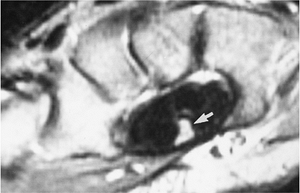

Ulnar lunate abutment syndrome is associated with ulnar positive variance (Fig. 9-55).

Patients present with ulnar wrist pain that often is exaggerated by ulnar deviation of the wrist.

Radiographs show ulnar positive variance

and sclerosis or cystic change in the lunate and triquetrum. Features

are more easily demonstrated with MRI for early bone, cartilage, and

FIGURE 9-56 MR images in patients with ulnar lunate abutment syndrome. (A) T1-weighted image shows low signal intensity in the lunate and adjacent triquetrum. (B) Gradient echo coronal shows displacement of the radial aspect of the triangular fibrocartilage (open arrow) and a peripheral tear (black arrow).